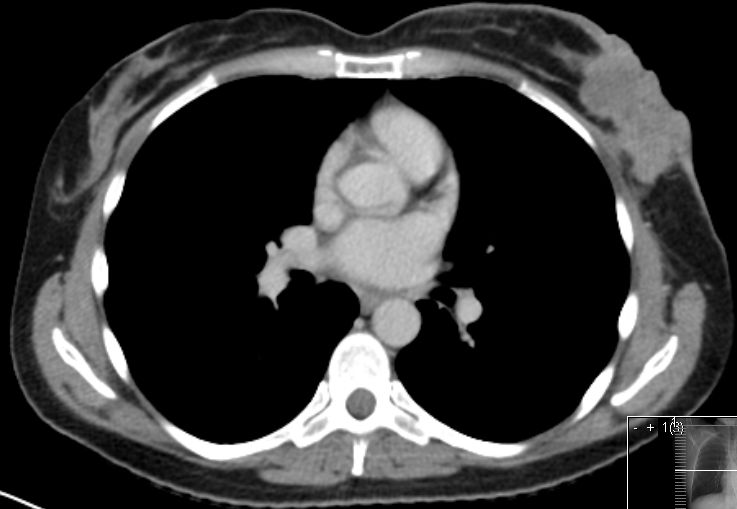

Mammographie,

MRT,

Sonographie,

Thermographie,

Szintigraphie,